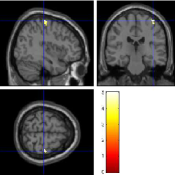

Once the reduced FOV images are available, the proposed pMRI 4D-UWR-SENSE algorithm and its early UWR-SENSE version have been utilized in a final step to reconstruct the full FOV EPI images and compared to the mSENSE Siemens solution. For the wavelet-based regularization, dyadic Symmlet orthonormal wavelet bases [48] associated with filters of length 8 have been used over resolution levels. The reconstructed EPI images then enter in our fMRI study in order to measure the impact of the reconstruction method choice on brain activity detection. Note also that the proposed reconstruction algorithm requires the estimation of the coil sensitivity maps (matrix in Eq. (2)). As proposed in [4], the latter were estimated by dividing the coil-specific images by the module of the Sum Of Squares (SOS) images, which are computed from the specific acquisition of the -space centre (24 lines) before the scans. The same sensitivity map estimation is then used for all the compared methods. Fig. 5 compares the two pMRI reconstruction algorithms to illustrate on axial, coronal and sagittal EPI slices how the mSENSE reconstruction artifacts have been removed using the 4D-UWR-SENSE approach. Reconstructed mSENSE images actually present large artifacts located both at the centre and boundaries of the brain in sensory and cognitive regions (temporal lobes, frontal and motor cortices, …). This results in SNR loss and thus may have a dramatic impact for activation detection in these brain regions. Note that these conclusions are reproducible across subjects although the artifacts may appear on different slices (see red circles in Fig. 5). One can also notice that some residual artifacts still exist in the reconstructed images with our pipeline especially for . Such strong artifacts are only attenuated and not fully removed because of the high level of information loss at .

| mSENSE | 4D-UWR-SENSE | ||

| Axial |  |

|

|

| Coronal | |||

| Sagittal | |||

| Axial |  |

|

|

| Coronal | |||

| Sagittal |